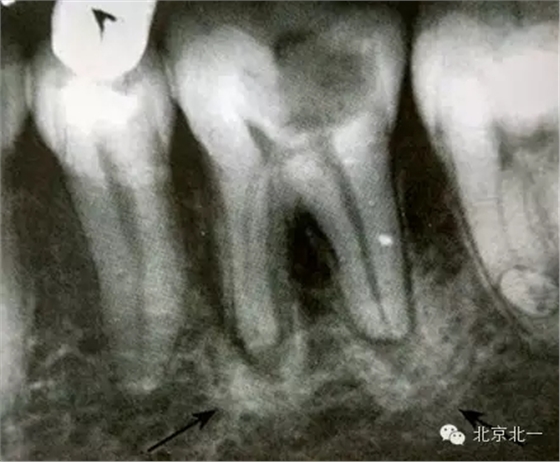

【CBCT表現(xiàn)】:發(fā)生致命性骨炎的環(huán)亞暢游牙體病變,其CBCT表現(xiàn)為圍繞根尖的骨質(zhì)密度增高區(qū),骨小梁增多增粗,骨髓腔變窄甚至消失,與正常骨組織分界不明顯。根尖部牙周膜間隙可增寬,根尖無(wú)增粗膨大。

根尖片顯示D6深齲,根尖低密度區(qū)周圍骨小梁增粗、增多,骨質(zhì)密度增高,骨髓腔變小(黑色箭頭)。